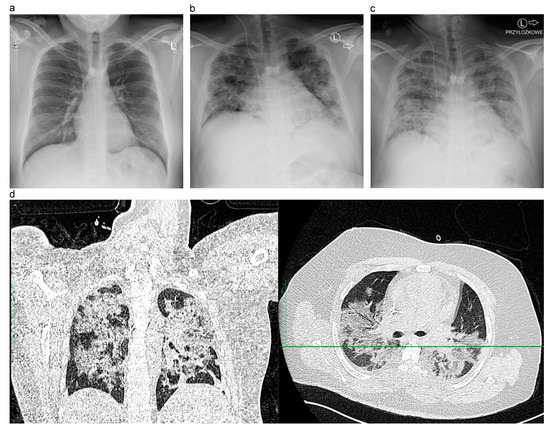

COVID-19 during Early Phase of Autologous Stem Cell Transplantation

Abstract

:1. Introduction

2. Discussion

3. Conclusions